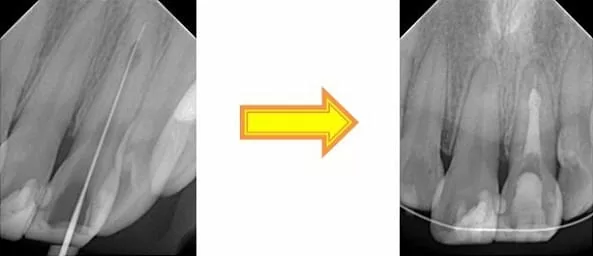

由於牙髓內部產生不規則的破壞,所以利用顯微鏡探照根管內部,以利做完善的根管清創,將細微死角徹底清潔。

根管插針先測量根管長度,以利完全的封填 根管封填

根管治療前與治療後比較